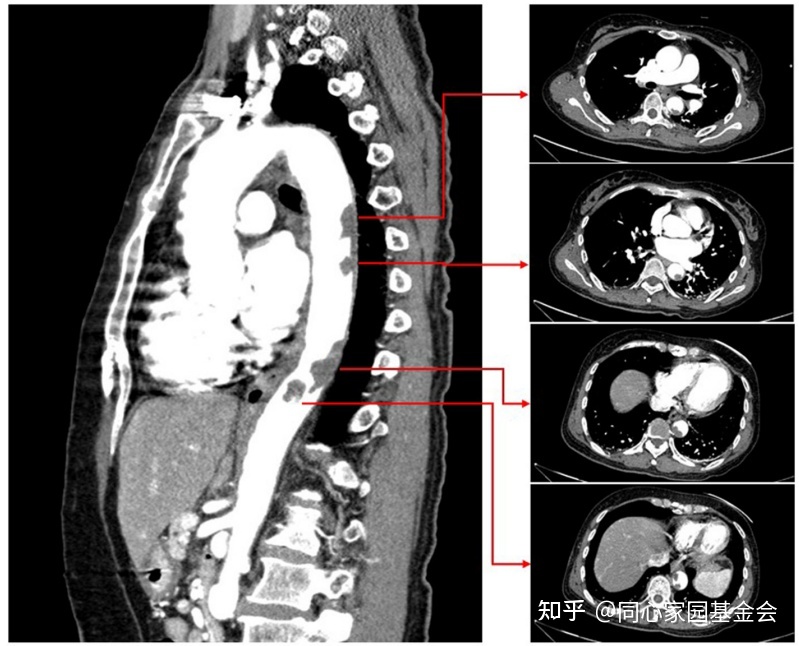

CTA显示降主动脉有大量附壁血栓(图3)。开始给予依诺肝素(8000 IU/天)。

图3:CTA显示巨大的降主动脉壁血栓。